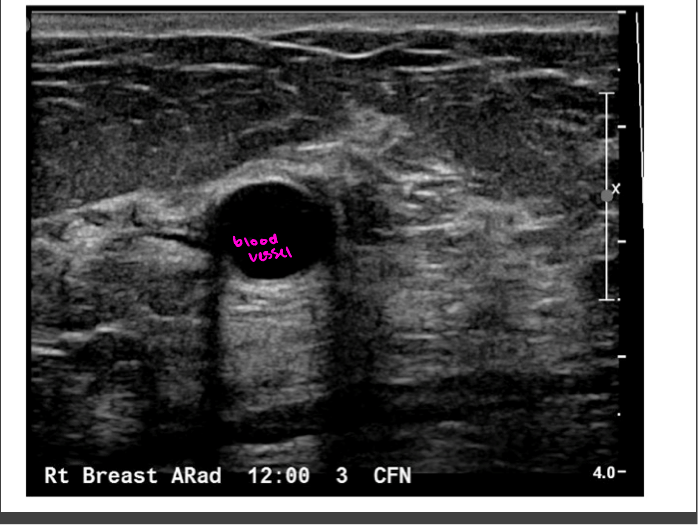

Ultrasound (cheap and easy)

Transmission of high-frequency sound waves through tissues to provide contrast and make images from the reflected waves (Echos)

Used for peds, OB, vascular imaging, ortho, renal, scrotal, ovarian

Used for guidance of interventional procedures (biopsies, thoracentesis)- good for use in real time

Echogenicity

Level of gray or brightness on an ultrasound image

Described in relation to surrounding tissues

Anechoic

no echos

Bladder, cystic fluid, gallbladder